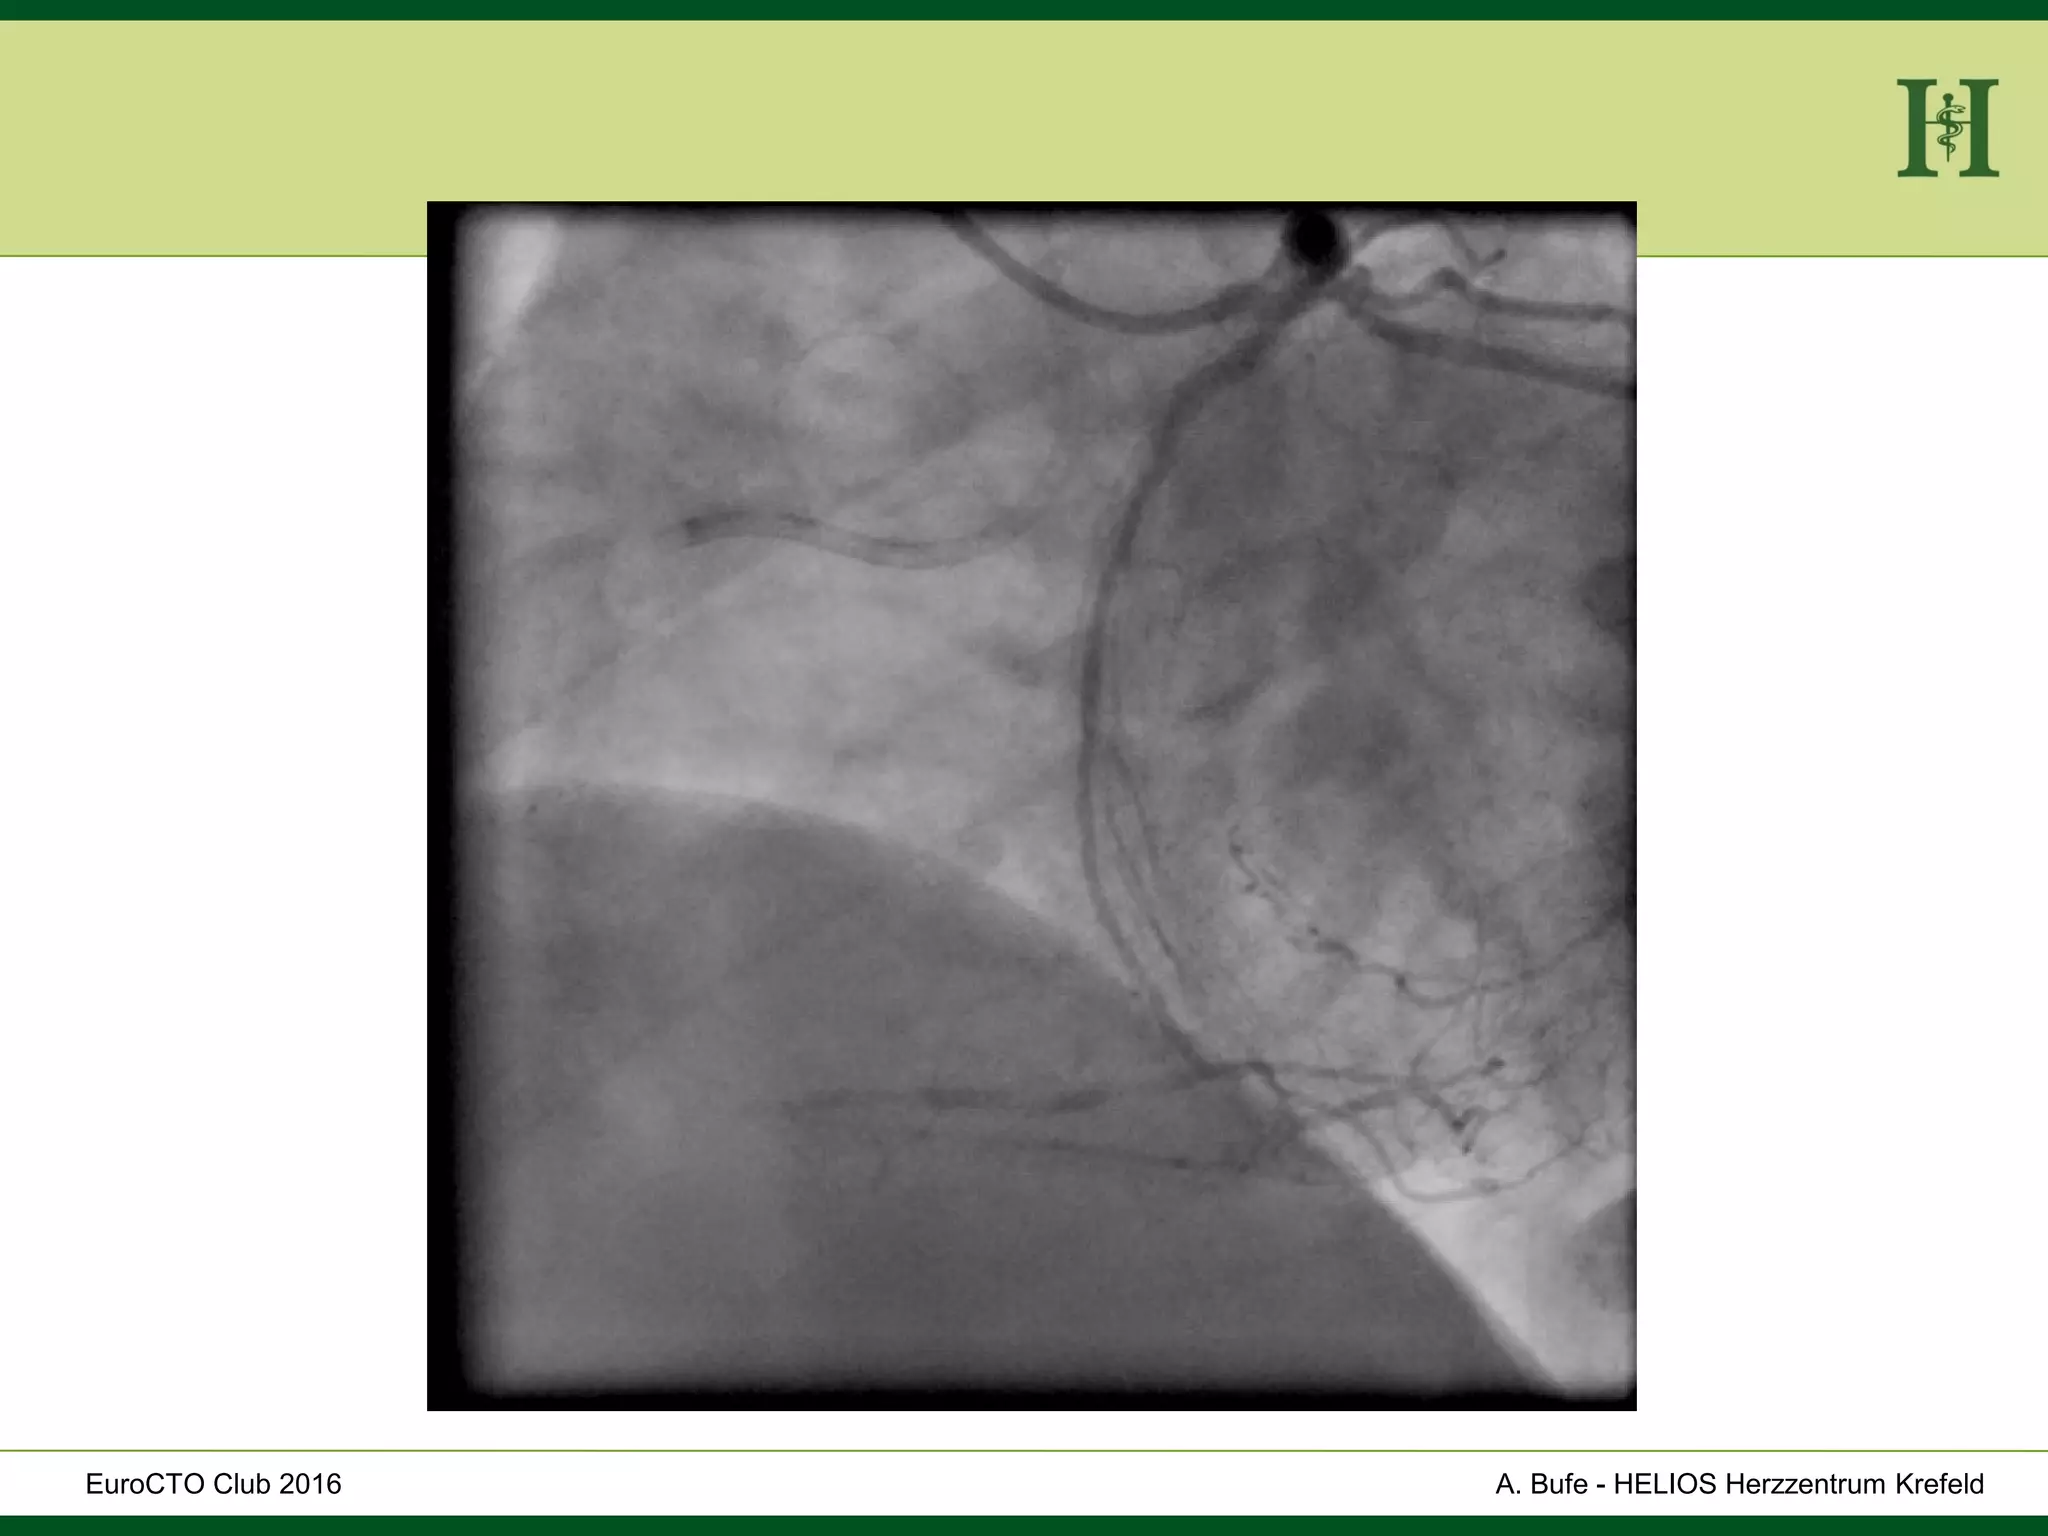

Male Patient, 55 years old

History:

 PCI 2015 with DES in LAD and in proximal RCA and

in PLD

 Angina pectoris CCS III for 7 months

 170cm, 75Kg

 RF: HLP, hypertension, smoking, HLP, familiy history

 Echo: Normal LV-Function, EF 65%

 Ischaemia inferior (MRI)